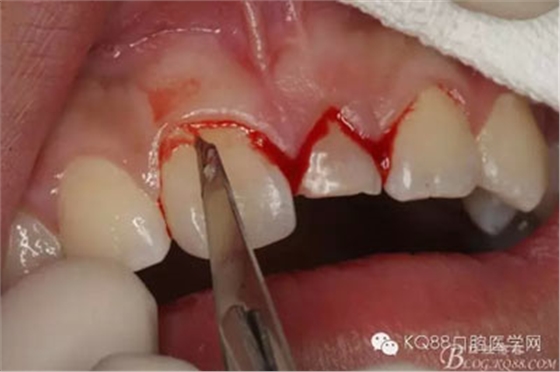

圖5.局部無痛麻醉下。行唇側(cè)齦溝內(nèi)切口